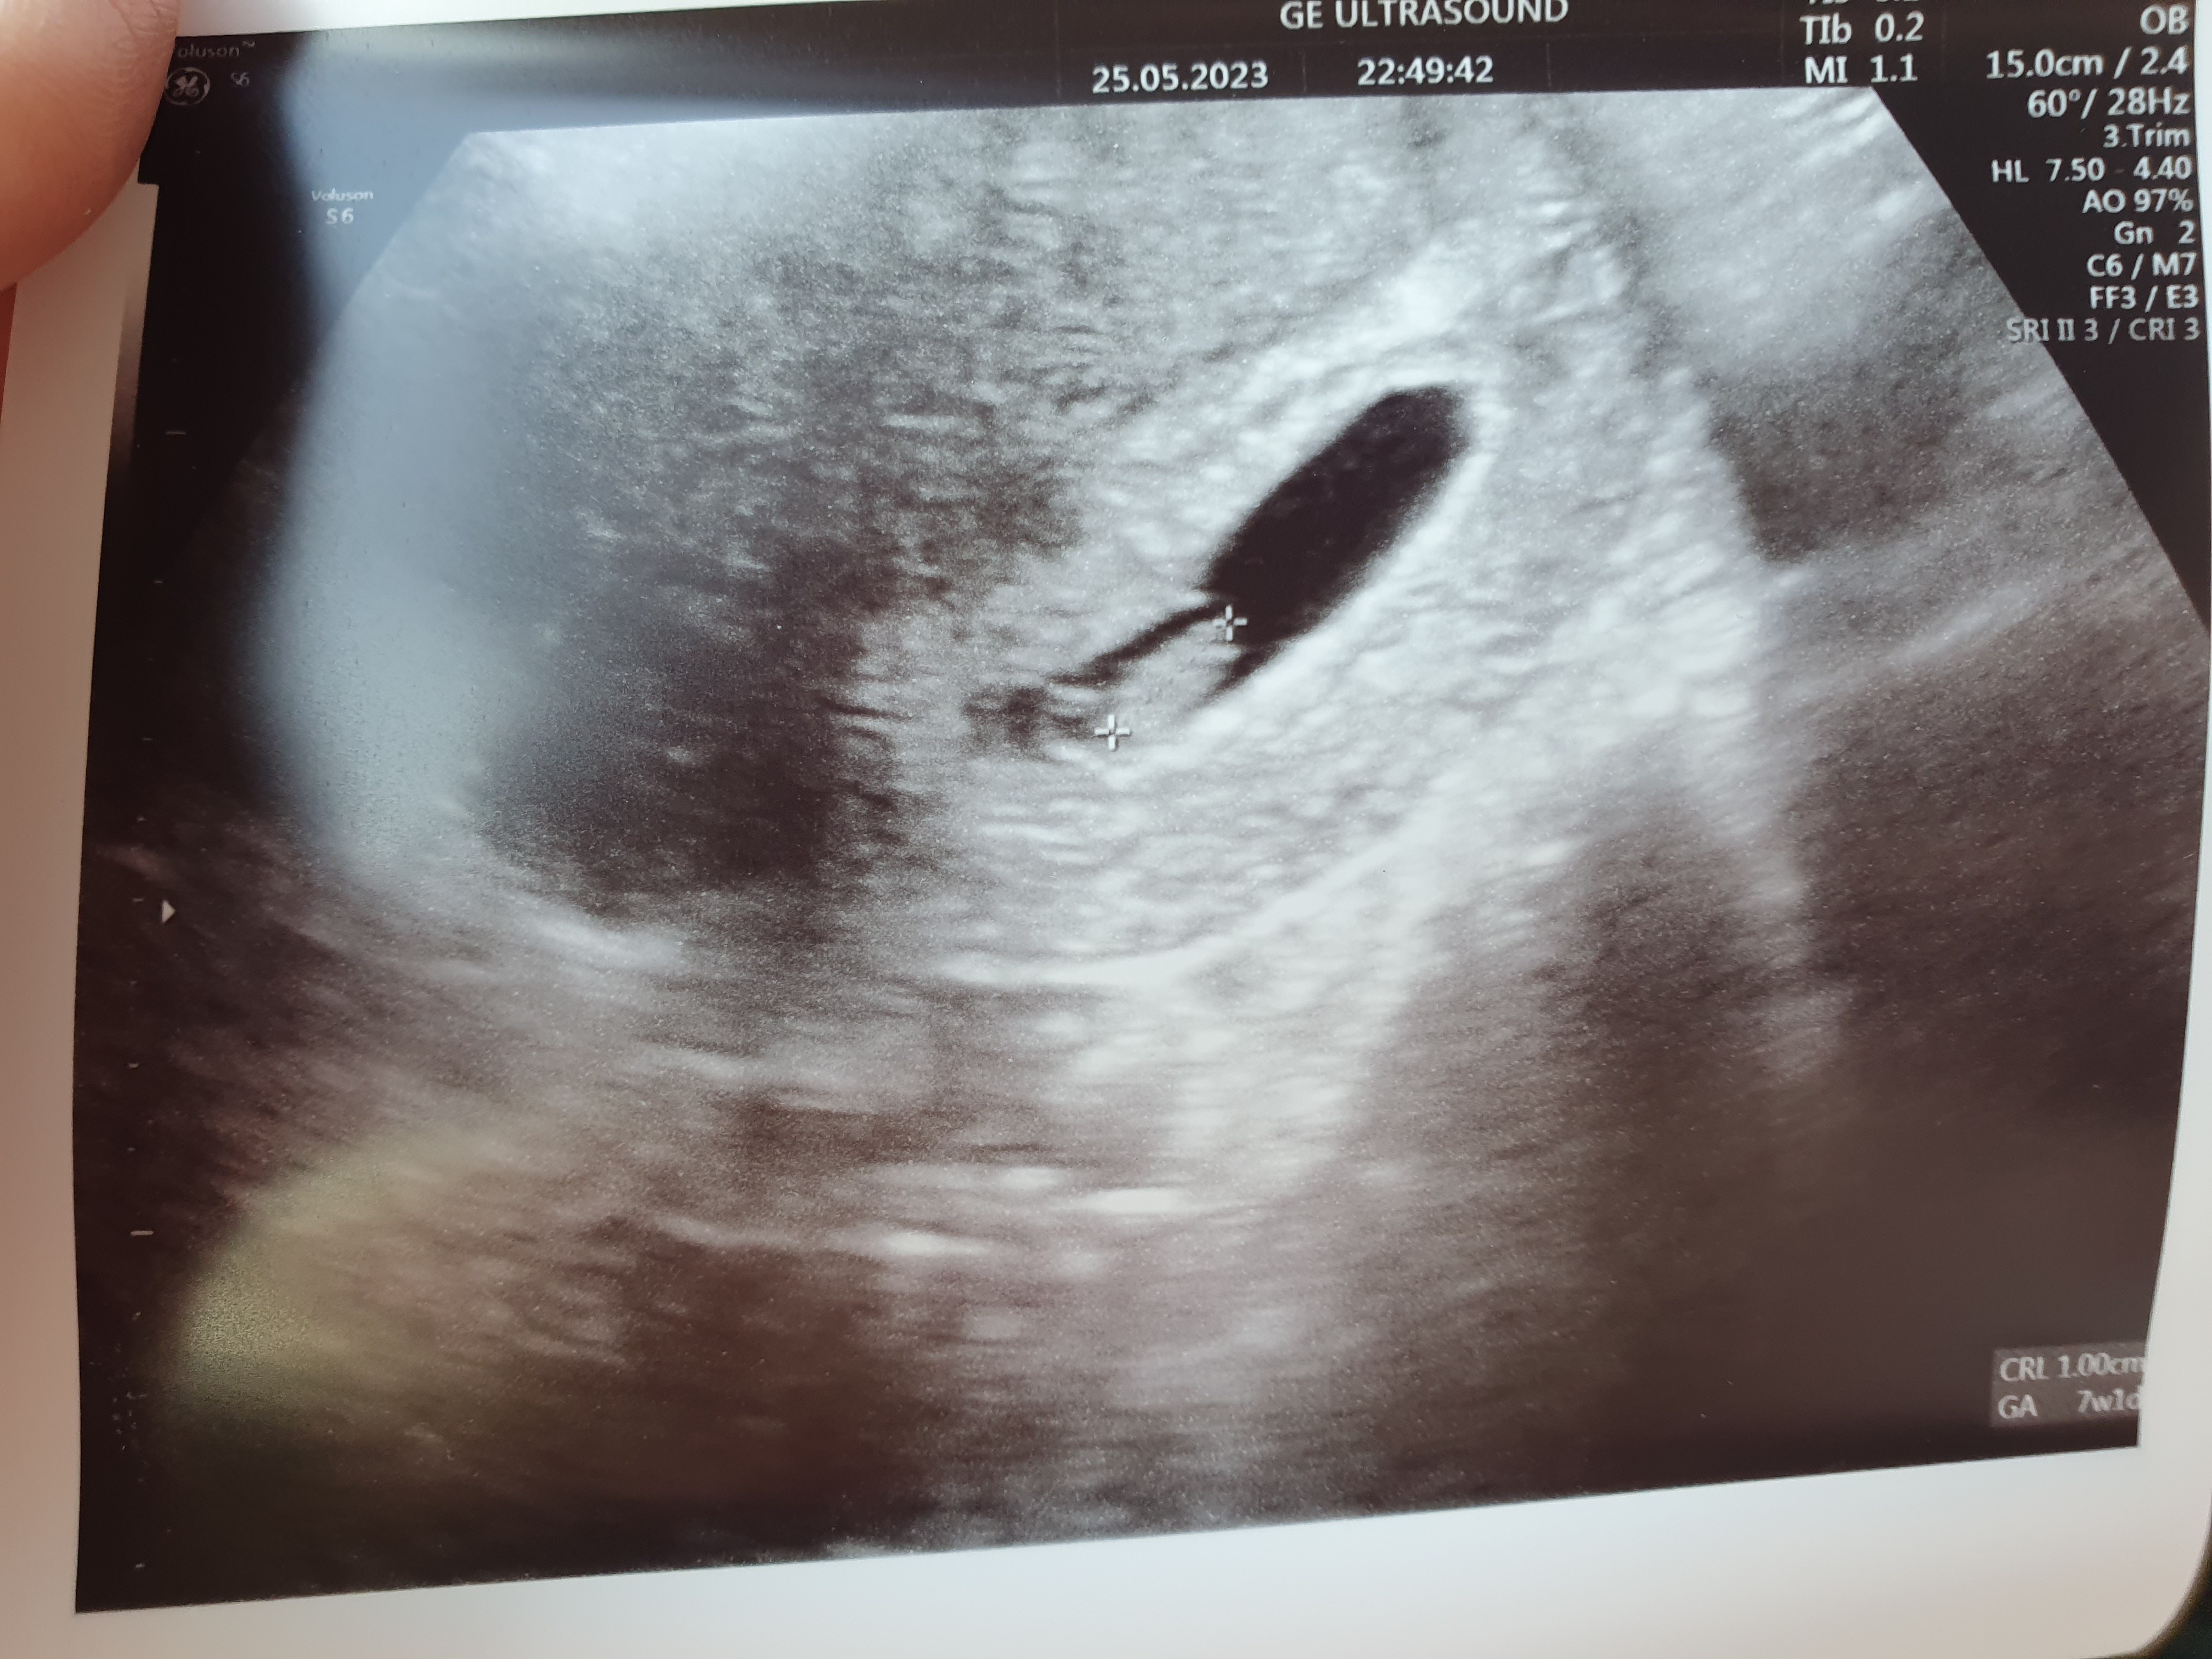

Ma 1 cm i bije mu 💚 popłakałam się już chyba 5 raz...

• 20230525_162611.jpg

20230525_162611.jpg

1,7 MB · Wyświetleń: 134